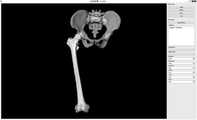

도 19는 부서진 대퇴골의 재건 결과이다.

19 is a result of reconstruction of the broken femur.